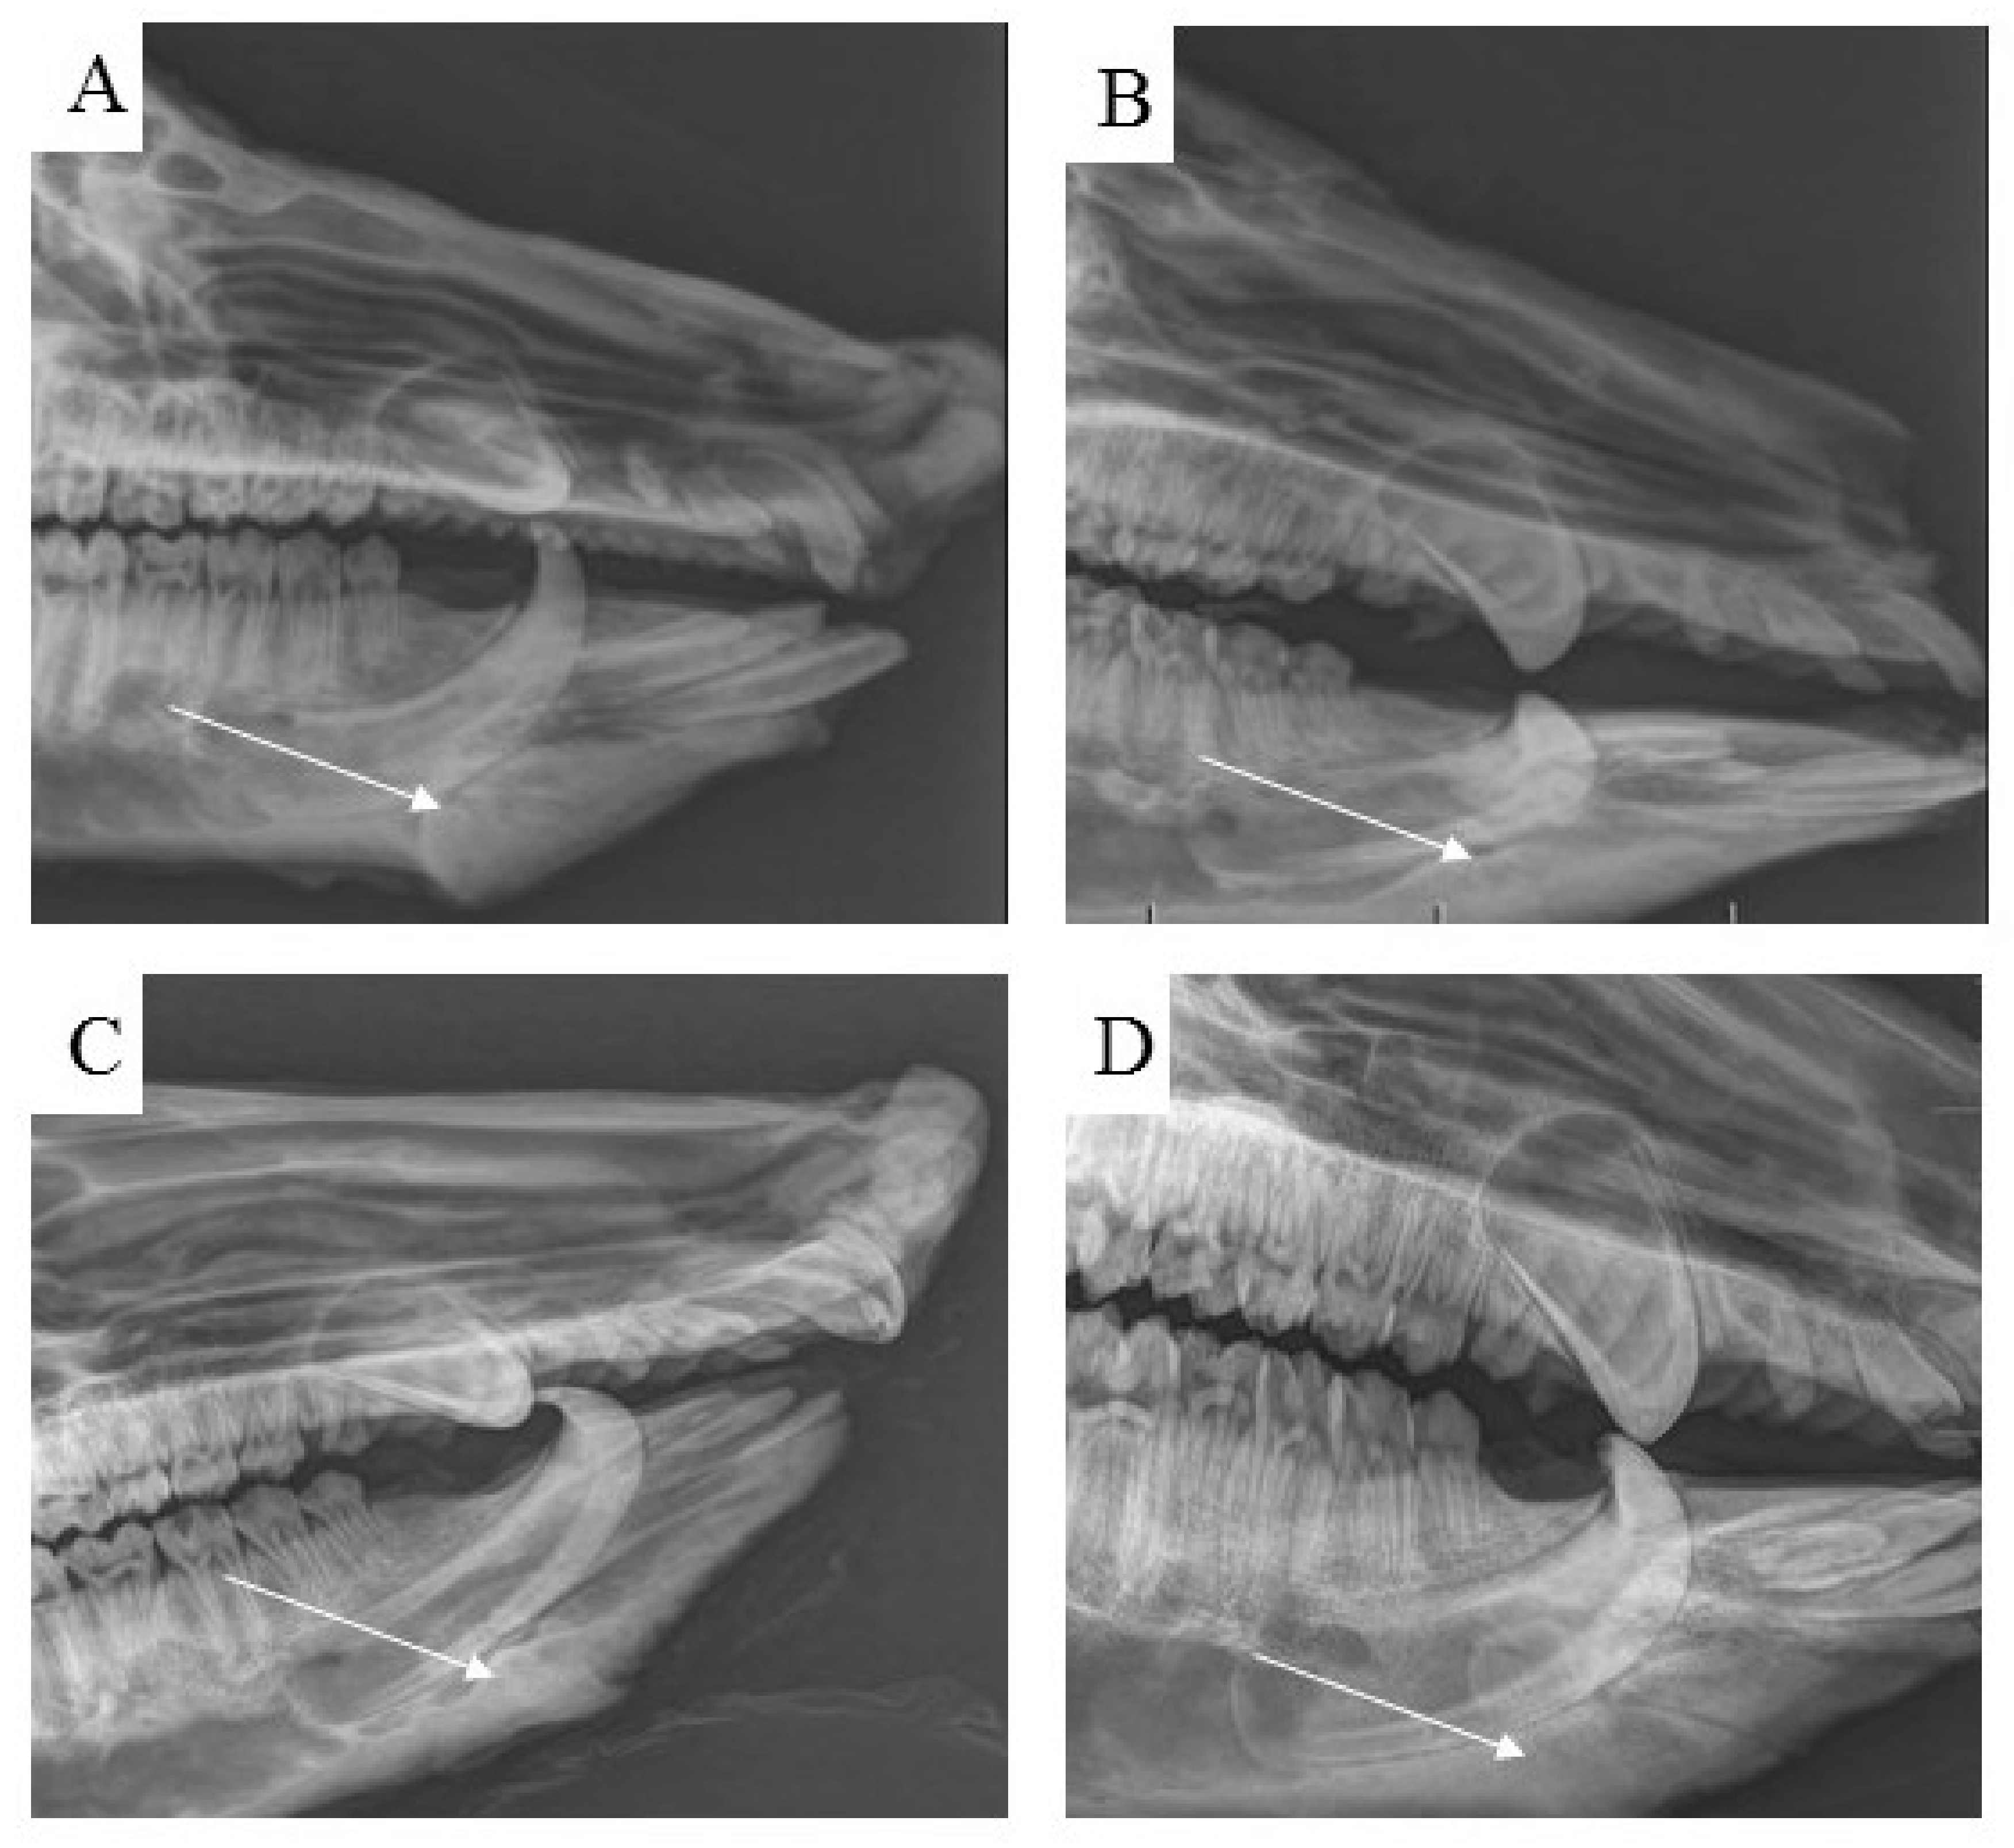

3.7. Radiological Assessment